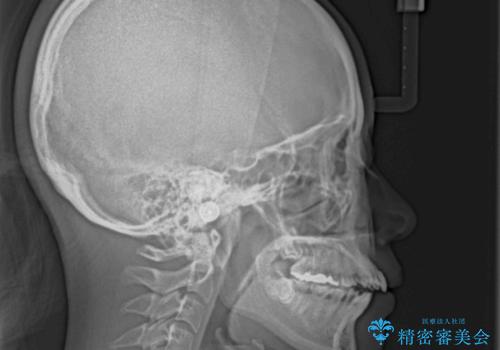

- 下の前歯のデコボコと、口元の突出感を改善したいと来院された患者様です。

突出感の強い上顎前歯をしっかりと後方移動させるため、上顎の裏側の補助装置(リンガルアーチ)とアンカースクリューを併用しています。

上下左右の第一小臼歯を抜歯して、目立ちにくいワイヤー装置で矯正を行いました。